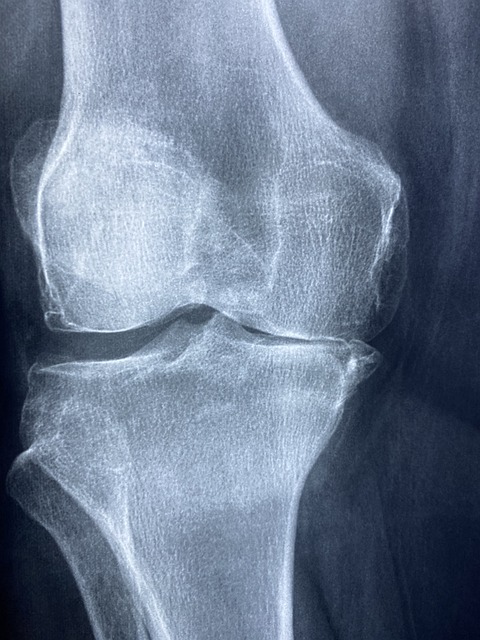

1. 염증 반응 완화 : 보스웰리아는 특히 관절염과 같은 염증성 질환의 증상 완화에 효과가 있다고 알려져 있습니다.

2. 통증 완화 : 보스웰리아는 자연스러운 통증 완화제로 작용합니다. 특히 관절 통증에 대한 완화 효과를 보여주며, 이는 연구로도 입증되었습니다.